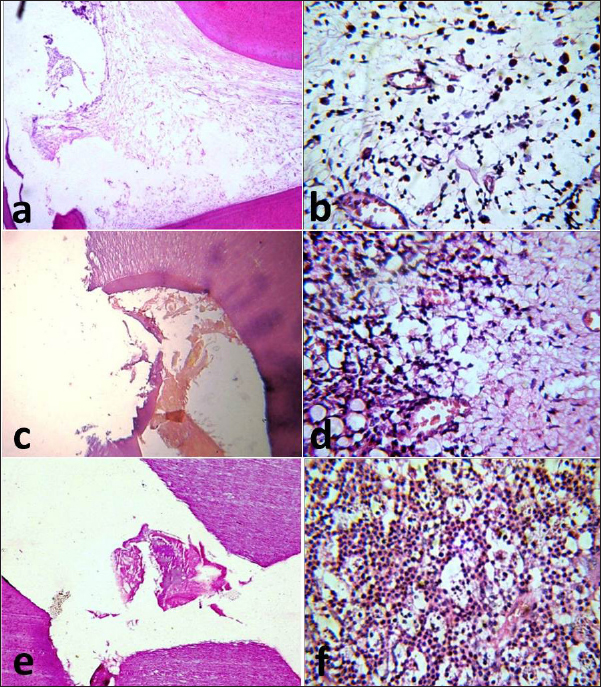

One month following pulp capping in azathioprine-immunosuppressed dogs, MTA exhibited a damaged odontoblastic layer opposite to the exposure site, areas of superficial necrosis, and loss of normal pulp architecture, without evidence of dentine bridge formation (Fig. 2a). Inflammatory cell infiltrates were seen in the deeper layer of the pulp (Fig. 2b). Subgroup B (BA subgroup) had the same pathological findings found in the MTA subgroup; however, partial dentine bridge formation and areas of newly formed fibrous tissue were seen in the middle part of the pulp (Fig. 2c and d). Subgroup C (Ca(OH)2 subgroup) exhibited the same pathological findings as the MTA subgroup (Fig. 2e) but the pulp tissue was heavily infiltrated with inflammatory cells (Fig. 2f).

Fig. 2. Photomicrographs of the immunosuppressed group after one month. MTA subgroup showing the exposure site without dentine bridge formation (a) and infiltration of the pulp with inflammatory cells (b). BA subgroup showing the exposure site with partial dentine bridge formation (c) and dilated and congested blood vessels with areas of fibrosis (d). Ca(OH)2 subgroup showing the exposure site without dentine bridge formation (e) and heavy inflammatory cell infiltration (f). The images (a), (c) and (e): H&E, X10 while (b), (d), and (f): H&E, X40.